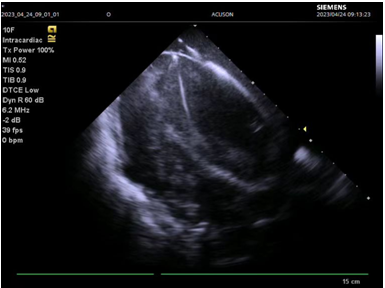

图三:心腔内超声指导下成功穿刺房间隔

此例手术由姚晓伟主任医师、韩稳琦主治医师、赵永勇主治医师通过心腔内超声指导下进行,通过心腔内超声精准构建心脏模型、直视下穿刺房间隔,后通过心腔内超声及左心房造影寻找狭窄的二尖瓣瓣口,并指引二尖瓣球囊扩张导管顺利经狭窄的二尖瓣口至左心室,在心腔内超声的指引下选择最佳位置以26mm球囊导管反复扩张狭窄的二尖瓣。术后第二天复查心脏超声,患者二尖瓣瓣口面积由术前0.67cm2扩大到术后1.69cm2,二尖瓣跨瓣压差由术前22mmHg降低至术后的16mmHg,左房前后径由术前94mm减小至术后92mm,左房左右径由术前109mm减小至术后102mm,并且球囊扩张后未引起明显的二尖瓣反流,患者心功能明显改善,自觉症状明显好转出院。

患者因“发作性气短20余年”之主诉入院,多次心脏超声诊断为风湿性心脏瓣膜病二尖瓣狭窄,此次因症状再发加重入院。经评估患者二尖瓣瓣口面积为0.67cm2,二尖瓣跨瓣压差为22mmHg,左房前后径94mm,左右径109mm,为重度风湿性二尖瓣狭窄伴罕见巨大左心房。在心内二科主任寿锡凌带领下,全科室充分讨论。因患者年龄大、基础情况差、无法耐受外科手术治疗,药物治疗不能解除瓣膜狭窄,只能选择经皮二尖瓣球囊扩张成形术。但鉴于患者巨大左心房已使心脏结构发生了巨大变化,单纯通过传统DSA影像结合经胸心脏超声指引下穿刺房间隔引起心脏破裂、心脏填塞、房间隔穿刺部位不佳影响手术操作、二尖瓣狭窄严重难以寻找二尖瓣瓣口、球囊扩张时球囊扩张位置不佳、术中难以即刻评估瓣膜扩张效果等均会导致手术失败进而威胁患者生命。考虑到心腔内超声宛如“心腔内的眼睛”可实时为术者提供心腔内的解剖结构毗邻关系,弥补传统DSA影像结合经胸心脏超声的不足,能为术者决策实时提供指导,确保手术能够安全、准确、顺利完成,最终决定为患者行心腔内超声指引下经皮二尖瓣球囊扩张成形手术。